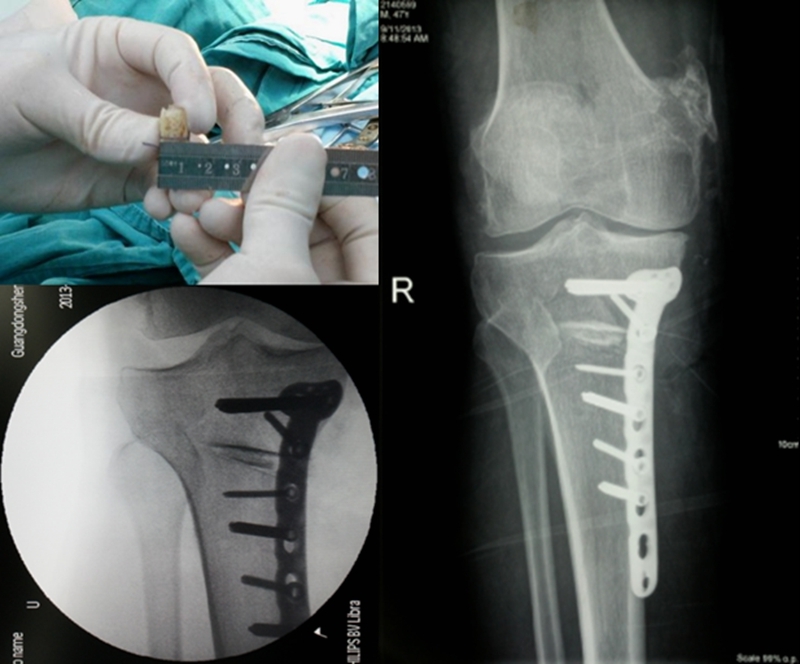

3D打印辅助截骨技术

陈国仙等利用3D打印技术辅助CWTHO术治疗膝内翻畸形骨关节炎患者20例,术前于Mimics软件设计并3D打印截骨导航模板,术中在模板辅助下行闭合楔形截骨。16例获随访,优良率达95%,1例出现腓总神经麻痹症状。3D打印截骨导航模板可精确辅助术中截骨,避免反复多次透视以及截骨,可获得良好临床疗效.

A.双平面截骨,第一刀沿水平面在胫骨后2/3进行截骨,保留外侧合页约10mm,第二刀沿冠状面在胫骨前1/3进行截骨,两刀截骨角度呈110°。B.撑开器逐渐缓慢加大骨缝,注意保留外侧合页。C.力线杆定位,撑开至力线杆经过Fujisawa点。D.进行内固定。

是否植骨?

认为可以不植骨:

Zorzi等研究发现OWHTO是否植骨不影响术后临床效果;Turkmen等认为内侧张开胫骨高位截骨术是治疗膝关节内翻畸形有效的手术方式,在保证精确截骨矫正畸形以及固定强度足够的前提下,术中不植骨也可取得满意预后。

认为需要植骨:

Aryee等认为撑开高度超过10mm需要植骨;El-Assal等则认为当截骨高度>14mm时进行骨移植或人工骨;Spahn认为撑开角度超过12°时需要植骨。

手术注意事项

发生“合页”骨折,固定不牢固,发生不愈合的几率大大增加,文献显示发生率在8.3%-18.2%;

Stoffel等发现如果合页处外侧皮质发生骨折,会导致截骨处微动,易导致骨折不愈合;

Dexel等也推荐如果发生外侧皮质骨折需要采用坚强的外固定和植骨材料。